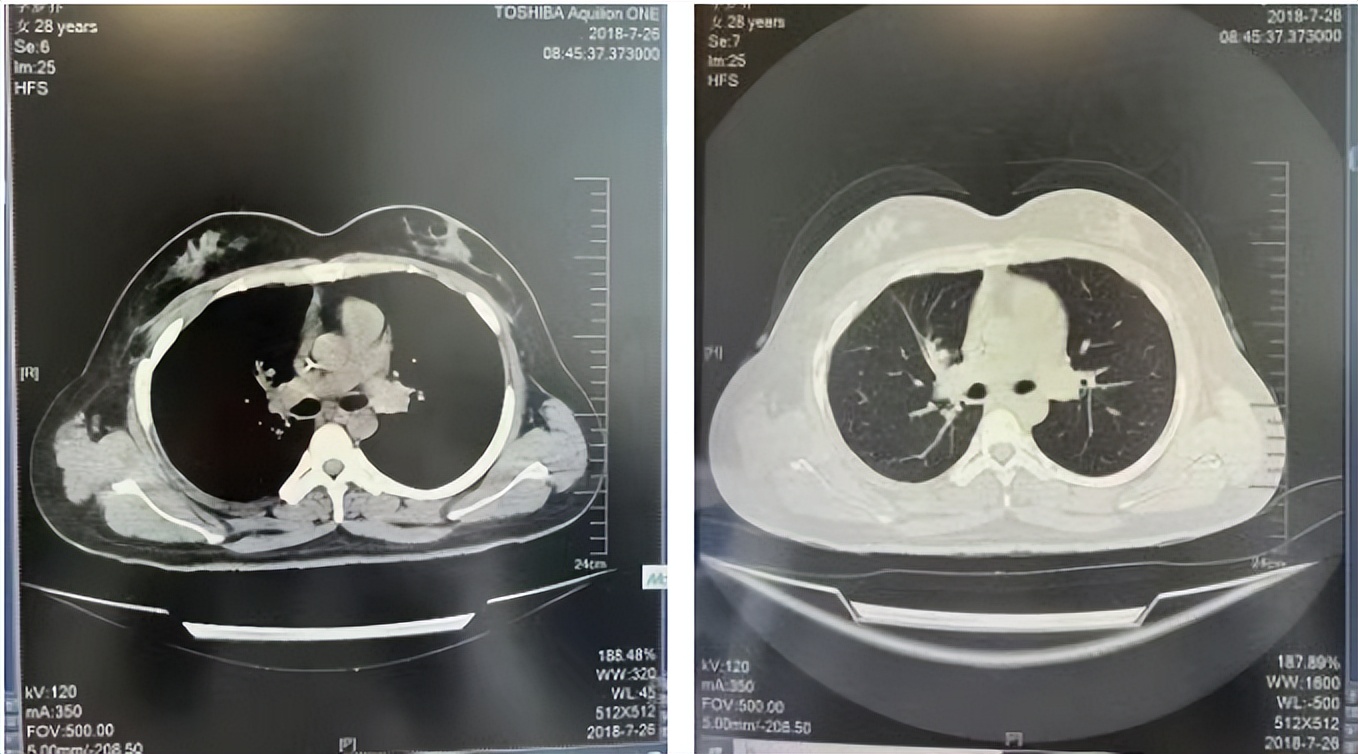

34岁,女性,无吸烟史饮酒史,既往体健。2015年11月无明显诱因出现咳嗽咳痰,痰为黄色粘液状,就诊于铁西华康医院,胸部CT示右肺上叶尖段可见结节影,邻近胸膜局限牵拉。2015年12月于胸科医院行肺肿物穿刺活检病理回报为肺腺癌。2015年12月16日全麻下行右肺上叶肺癌根治术及纵隔淋巴结清扫术,术后病理:肺组织中部分脉管内见腺癌组织,断端支气管旁淋巴结内见癌组织,淋巴结中见到转移癌(2/6),未行基因检测。

2016年1月复查CT提示支气管截断可见新发小结节,一线治疗采用培美曲塞+DDP方案化疗4周期(培美曲塞3.36,DDP 480mg)。化疗后复查胸部CT:右肺见不规则结节样影,最大层面大小约19mm*8mm,较前比较明显增大,疗效评估PD。2017.3-2017.4予单药多西他赛化疗3周期,疗效评估SD。2018年5月末复查CT提示结节较前增大,评效为PD,2018年6-10月予多西他赛+CBP化疗4周期,疗效评估SD。2022年5月患者出现活动后气短,复查胸部CT示右肺膨胀不良;右侧胸腔积液增多。胸腔积液包埋病理示符合肺腺癌细胞。行NGS基因检测:EML4:exon13-ALK:exon20融合。PD-L1(克隆号22C3)TPS<1%。

2018.07